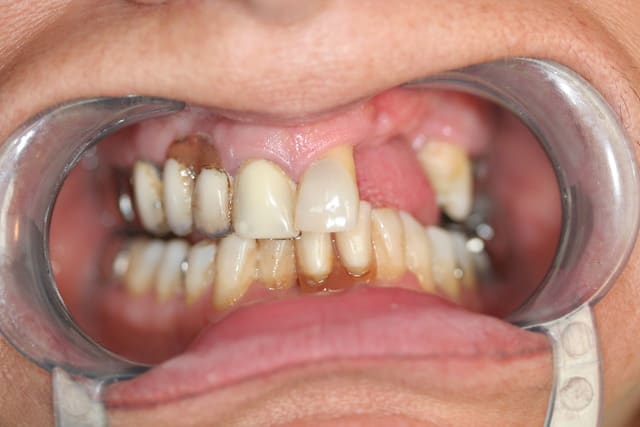

et ici ?? vous feriez quoi ?

32 et 42 pas mobiles

malheureusement, l'espace est réduit pour mettre deux implants.

comment avez vous déjà géré ce type de cas ??

le haut est déjà traité...

à propos du cas , j'ai vu avec la patiente cet aprem; nous avons décidé de faire un petit bridge provisoire de quelques mois et si (après traitement paro bien sure) les dents ne sont pas mobiles, on passera au bridge définitif. sinon, ce sera pose de deux implants en position 42-32 pour éviter une greffe que la patiente refuse.